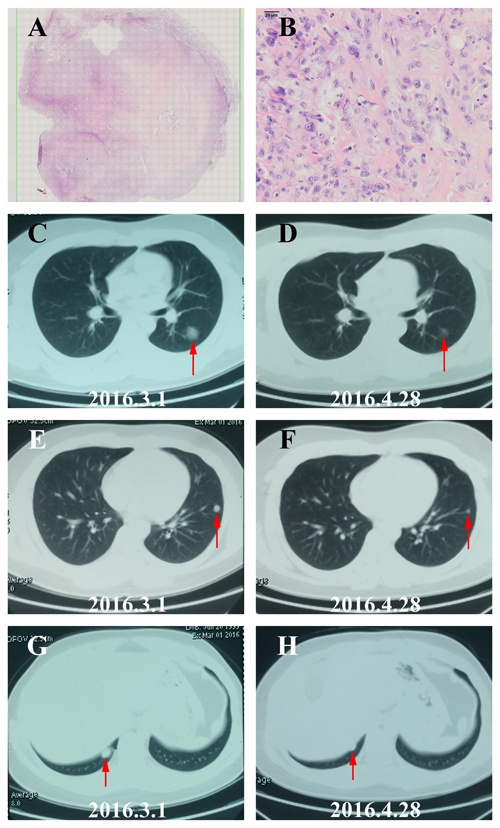

Ten patients received at least 1 full cycle of Apatinib treatment were eligible for efficacy analysis and 8 patients benefited from the Apatinib therapy (Table 1, Figure 2). The imaging and pathological data of 2 typical cases (1 case with osteosarcoma and another one with STS) were shown as follows. One 16-year-age male patient was first diagnosed to have femur osteosarcoma in August 2014. He was treated by adjuvant chemotherapy, wide resection of tumor, and postoperative chemotherapy with the MTX+DDP+ADM and MTX+IFO+DDP+ADM. After eighth cycles, the CT review found several lung nodes. CT guided biopsy confirmed diagnose of metastatic osteosarcoma in lung (Figure 3A-3B). The patient was treated with 2 cycles of chemotherapy including TXT and GEM. CT scan of the efficacy evaluation concluded progression disease (PD). Then the patient was treated with Apatinib at a 500mg dosage. After taking Apatinib for two cycles, CT review showed significant reduction of multiple metastatic lesions (Figure 3C-3H) and this patient was considered to have partial response (PR) according to Response Evaluation Criteria in Solid Tumors (RECIST) [21]. The patient is currently taking Apatinib with no progression. The second patient is a 36 year old female who was diagnosed to have high grade fibrosarcoma in the hip region in July 2012 (Figure 4A-4B). She was treated with wide surgical resection. In June 2015 the routine CT scan found a nodule in her right lower lung. The patient was treated with right lower lung resection and the postoperative pathological diagnosis was metastatic fibrosarcoma (Figure 4C-4E). After 2 cycles of postoperative chemotherapy regimen with ADM+IFO, the CT scan found multiple nodules in the lungs. The patient began Apatinib regimen with a dosage of 500mg. The first and second monthly CT scan showed a stable disease (SD) (Figure 4F-4I) according to RECIST and she continues to be in stable status 12 months after treatment.

Figure 3: The image and pathological data of one PR patient with lung metastatic osteosarcoma. A. HE staining of the biopsy tissue from the Lung metastatic lesion (10×). B. HE staining of the Lung metastatic lesion demonstrated typical histopathological features of osteosarcoma (40×). C.-H. The repeated Chest CT showed the result of partial response (PR) with the volumes of lung metastases tumor reducing evidently in 2 months.